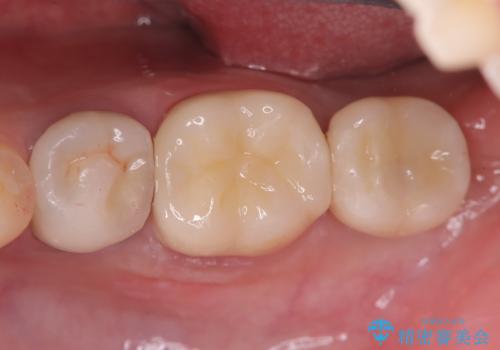

また、左下6番には形態が不自然で適合不良のセラミックインレーが装着されていたため、二次カリエスのリスクを考慮し、オールセラミッククラウンによる治療を行いました。

手術は1回で完了し、被せ物を装着するまでの治療期間も約3か月と、身体的・時間的な負担を抑えることができます。